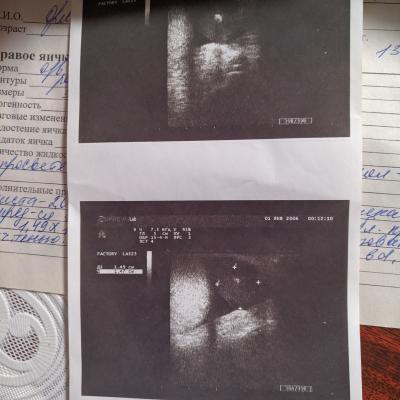

Здравствуйте, прошел УЗИ мошонки, так как было заметно увеличение, пол года назад проходил было диагностировано гидроцеле, кисты, киста правого яичка с кальцинатом, планово прошел повторно через пол года, и заключение такое: В паринхиме придатка мелкая киста 2,0мм Между оболочками в области придатка определяется гипоэхогенное опухолевидное образование, содержит Са диаметром 3,1мм с акустической тенью. Какое обследование необходимо пройти? какие анализы сдать? Фото результатов УЗИ прикрепляю

Здравствуйте! Сдайте кровь на AFP (альфа-фетопротеин) ХГЧ (хорионический гонадотропин человека) ЛДГ (лактатдегидрогеназа). С результатами покажитесь онкоурологу, который, возможно, назначит дополнительное обследование. Удачи!